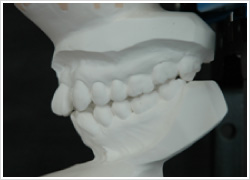

術者が(顎関節に負担のかからない)本来の顎位へ誘導すると、この患者さんは傾いて生えた左上の親知らずが他の歯より先に下の歯とぶつかってちゃんと咬めていないことわかります。

この様にずれた状態で診断をすると、治療方針が変わってきます。当院では、正しい顎の位置で治療方針を立てます。

患者さんの習慣的な顎位と本来の正しい顎位の差を見るためのデータです。このずれがどれくらいあるか、検査の後の診断時にお示しします。